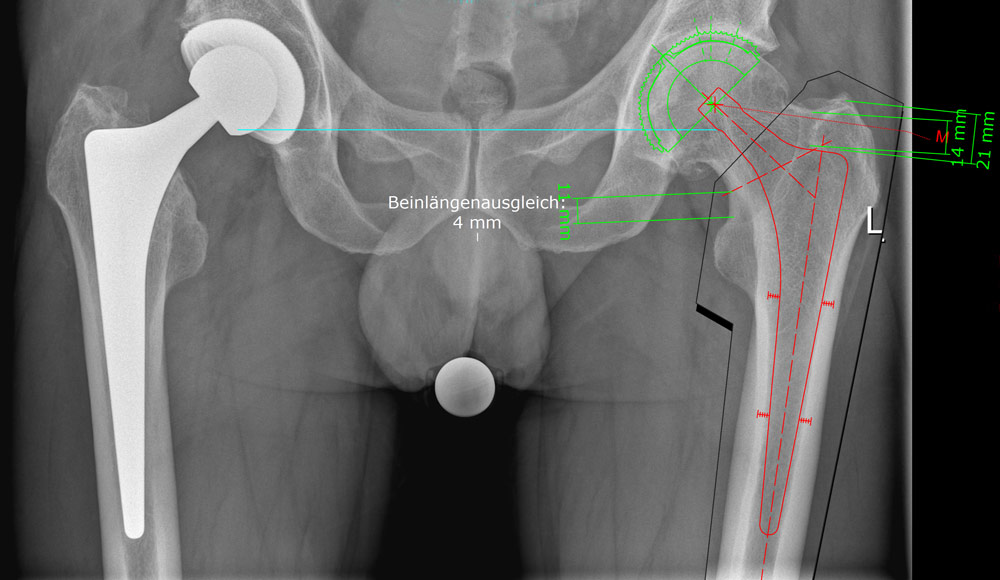

Künstliches Knie- oder Hüftgelenk: Das Endoprothetikzentrum am EvKB

Informationen zum Ersatz von Hüft- und Kniegelenken finden Sie auf der Seite unseres Endoprothetikzentrums.